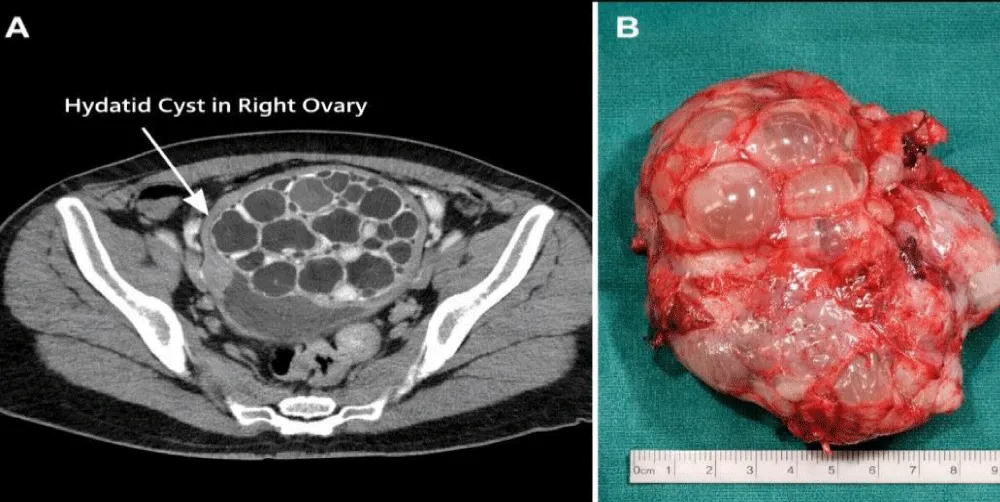

Computed Tomography (CT): Well-defined cystic lesion with internal daughter cysts, producing a honeycomb appearance (Figure 1A). No hepatic or pulmonary lesions were detected.

Figure 1: (A) CT scan showing a multilocular cystic lesion with daughter cysts producing a honeycomb appearance. (B) Macroscopic specimen of the ovarian cyst showing multiple daughter cysts filled with clear fluid.

Right adnexectomy was performed without rupture of the cyst. Macroscopic examination revealed multiple daughter cysts filled with clear fluid (Figure 1B).